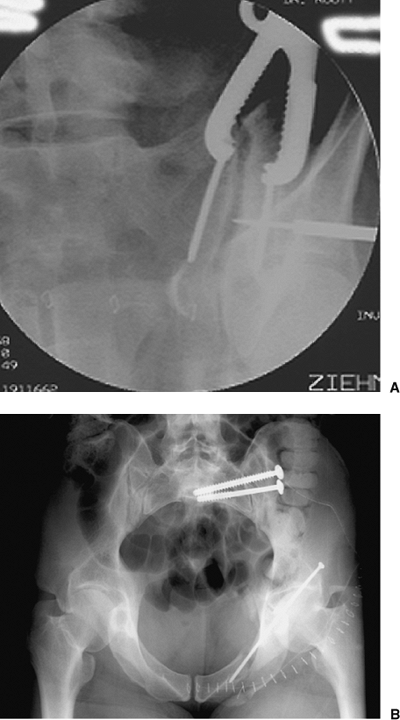

injury (Fig. 39.9).

Figure 39.9. A.

An iliosacral lag screw is targeted for reduction of a SI joint dislocation. This patient was hemodynamically unstable after appropriate resuscitation. The screw was used to achieve urgent posterior-pelvic stability. B. As the lag screw is tightened, the reduction is improved but is not anatomical. The SI manipulated screw reduction can be revised at a subsequent surgery through use of open reduction when the patient’s clinical condition is optimized. In such situations, this lag screw functions as an internal posterior-pelvic antishock clamp. |

Figure 39.10. A.

Through surgeon’s use of anterior exposure of the SI joint, the reduction clamp is applied between two screws across the joint and then is used to manipulate and hold the open reduction. The guide pin for a cannulated iliosacral screw is percutaneously inserted as shown on this intraoperative fluoroscopic image. B. Iliosacral screws were used to definitively stabilize the SI joint after open reduction. The initial lag screw compressed the joint while the subsequently inserted, fully threaded, iliosacral screw was used to fortify the SI fixation construct. |